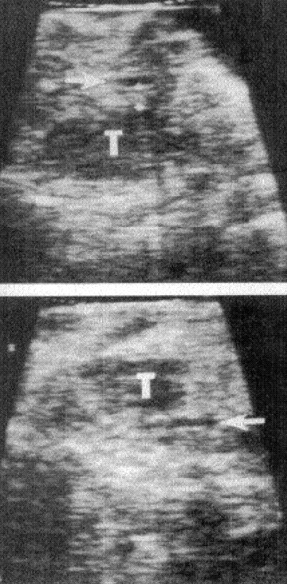

- באולטרה-סאונד תוך-ניתוחי אפשר למקם את הנגע ולזהות נגעים נוספים בלבלב או במקומות אחרים סמוכים (תצלום 33.9).